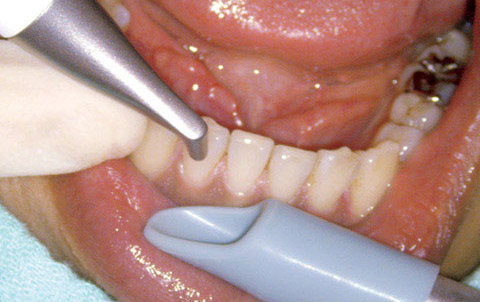

図4 同、下顎右側舌側部分。

図5 同、上顎前歯舌側部分。